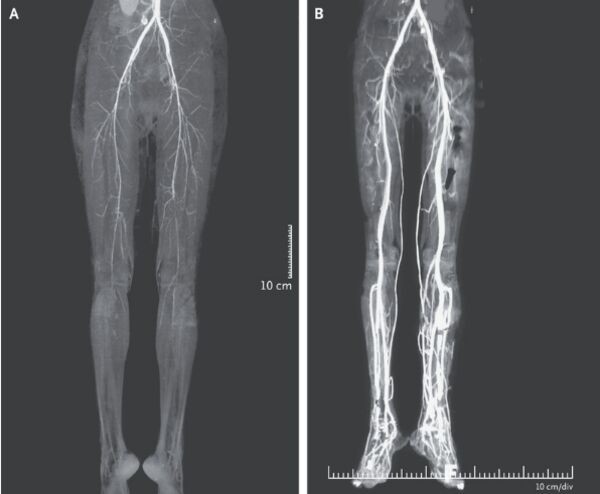

Ảnh chụp CT cho thấy động mạch ở cả 2 chân của cô đã bị thu hẹp, do đó làm giảm lưu lượng máu đến khu vực này.

Tuy nhiên, việc điều trị này hơi muộn nên nó không ngăn chặn được tình trạng hoại tử 1 ngón chân trái của cô. 2 tuần sau khi điều trị tích cực, chụp CT (chụp cắt lớp vi tính) cho thấy lưu lượng máu ở cả 2 chân được cải thiện.